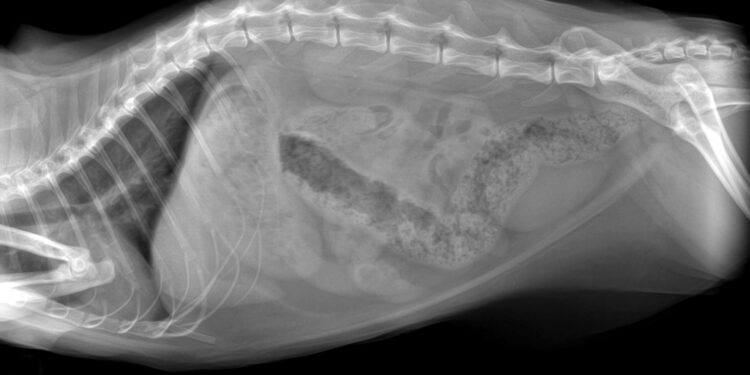

Kaip diagnozuojamas fekalinių masių susikaupimas

Gydytojas gali nustatyti šį sutrikimą atlikdamas apžiūrą ir tiesiosios žarnos tyrimą pirštu. Jei yra įtarimas, kad užsistovėjusių išmatų kamštis yra giliau storajame žarnyne, gali būti paskirta pilvo rentgeno nuotrauka, kuri tiksliai parodo jų lokaciją.